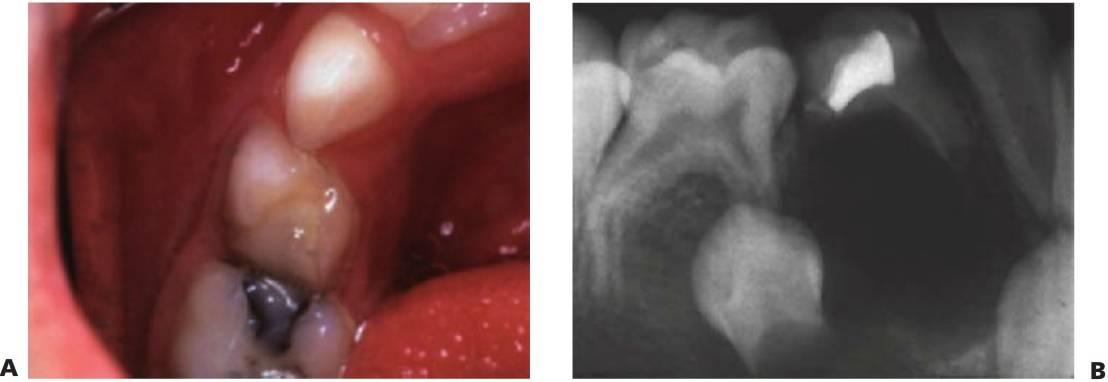

Dolor

Los pacientes más jóvenes, con frecuencia, varían al informar de su dolor y muchas veces los padres no lo aprecian hasta que el dolor se hace grave y prolongado. Los síntomas de dolor grave, prolongado, espontáneo o nocturno sugieren una pulpitis irreversible o un absceso dental (fig. 6.3B). Una historia de necesidad repetida de analgésicos también parece indicar necrosis pulpar. Con frecuencia, el dolor dental se resolverá una vez que un conducto sinusal establezca un drenaje y, por tanto, alivie la presión. En estos casos, la lesión subyacente sigue estando presente y debe resolverse pese a la falta de molestias evidentes.

Inflamación

La inflamación alveolar, sobre todo la que afecta a la reflexión vestibular y la hinchazón facial, la decoloración coronal y la presencia de un seno indican una necrosis pulpar y la formación de un absceso (fig. 6.3B).